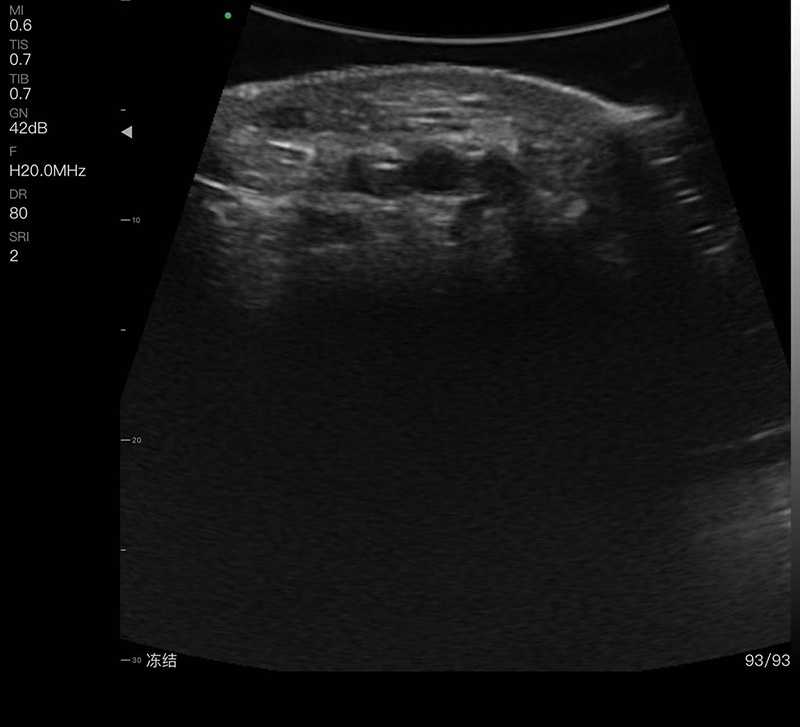

带指套探头的掌上彩超,小小的掌超主机放在口袋可随处走,手指套着探头即可完成打图成像,让手不再需要握着探头而可解放出来还能拿其他东西,特别适合术中等应用

- 探头频率:16/20MHz

- 扫描深度:10/20/30/40mm,可调

- 扫描角度:R20

- 显示模式:B、B/M、COLOR、PDI、PW